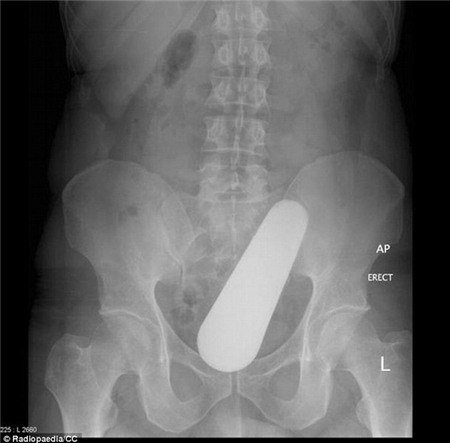

Đây

là hình chụp X-quang của một người đàn ông 40 tuổi. Trong trực tràng

của là một cái chày cán. Ông nói rằng mình trượt tay khi đang nấu món ăn

Malaysia khiến nó rơi vào trong trực tràng.